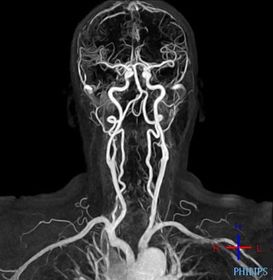

Resonancia Magnética Imagen por resonancia magnética (MRI). Es una técnica diagnóstica no invasiva que usa los campos magnéticos para detectar cambios sutiles en el tejido cerebral (1)